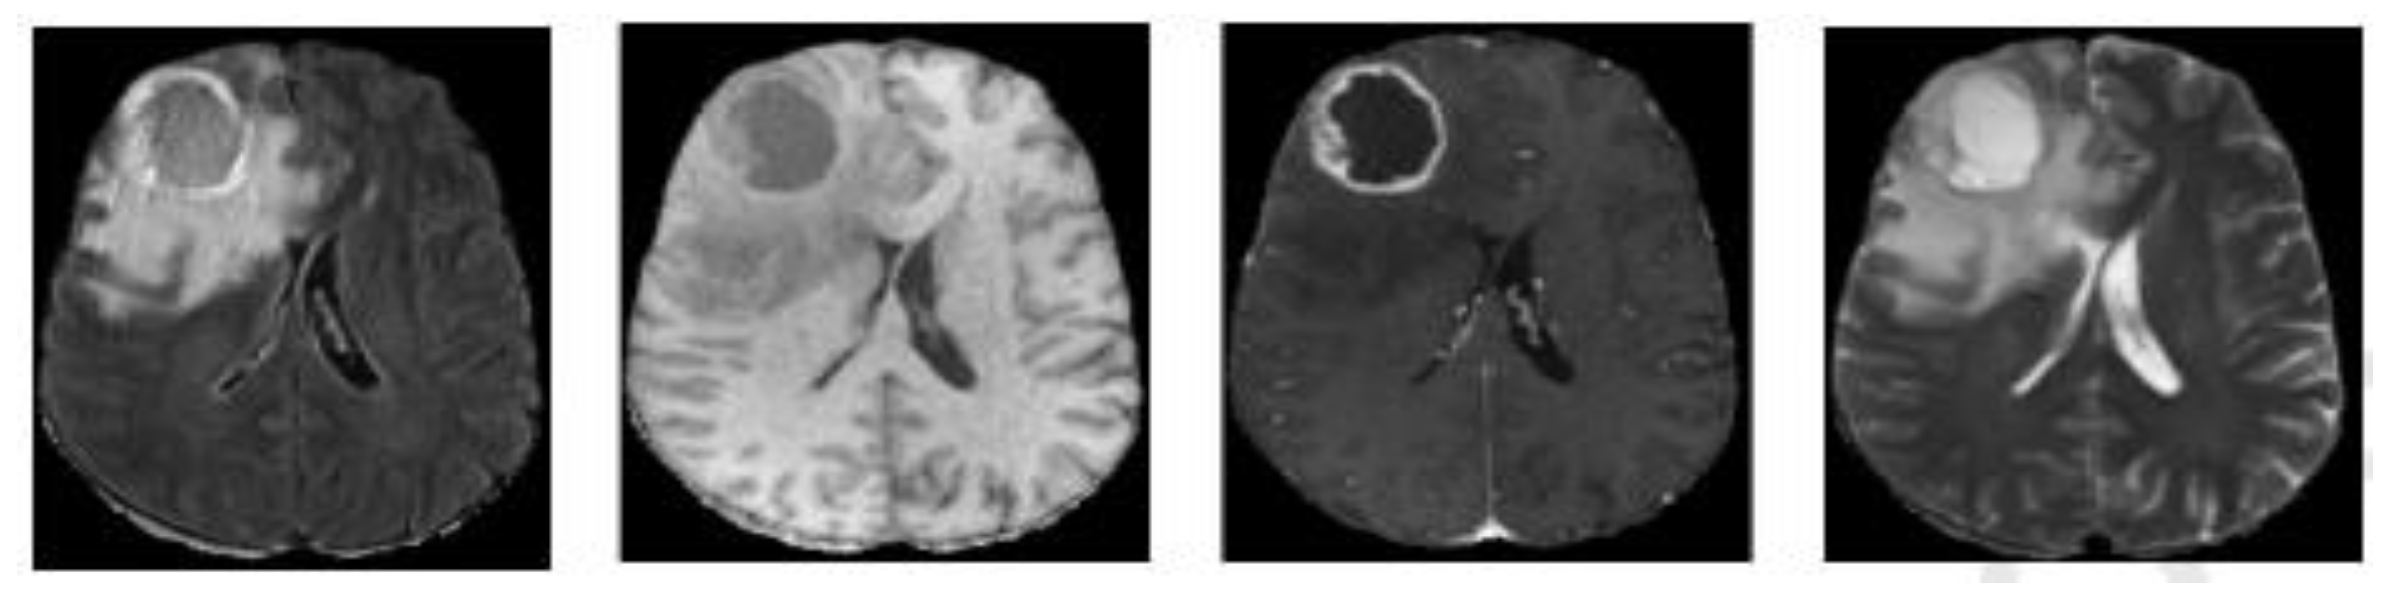

2.1. Data and Data Preparation

2.1.1. Dataset